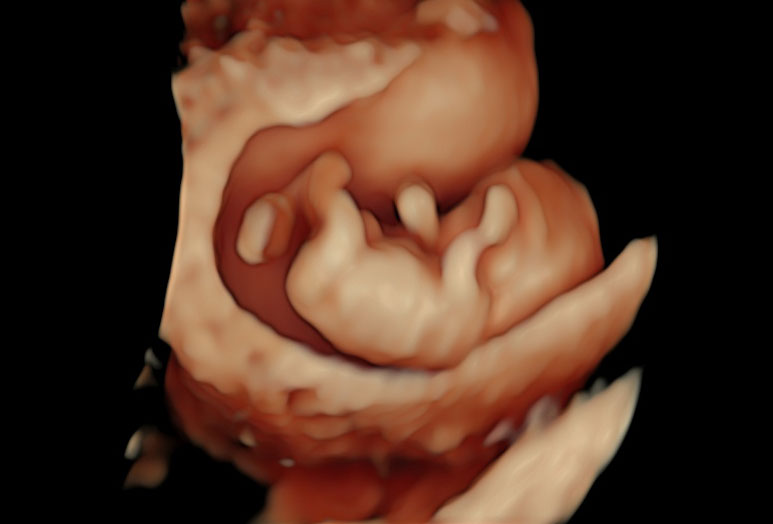

Die Untersuchung ist eine Kombination aus einer Ultraschalluntersuchung (First-Trimester-Screening) mit Darstellung von Nackentransparenz, Nasenbein und anderer Ultraschallmarker kindlicher Chromosomenstörungen, sowie einer Bestimmung zweier Hormone im mütterlichen Blut:( APP-A und freies ß-HCG.

Das First-Trimester-Screening mit Nackenfaltenmessung sollte jedoch auch nach einem Harmony Test durchgeführt werden. Denn es können trotz unauffälligem NIPT Test eine erhöhte Nackentransparenz oder andere kindlichen Auffälligkeiten vorliegen. Es muss jedoch nach einem NIPT keine Risikoberechnung und Hormonbestimmung mehr durchgeführt werden.

Beim First-Trimester-Screening werden folgende Strukturen untersucht: